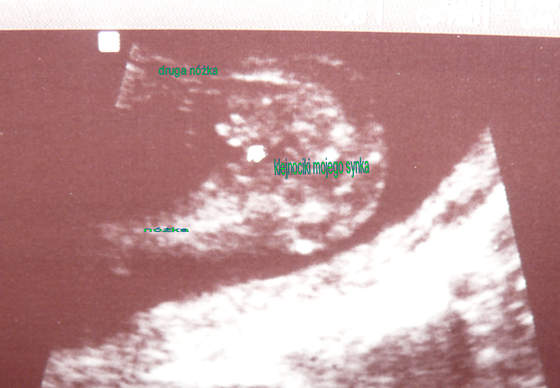

witajcie jestem majowka 2010:-) ogladam sobie wasze zdjecia z USG i moge powiedziec na 100% ze bedziesz miala coreczkepatrzac na twoje USG